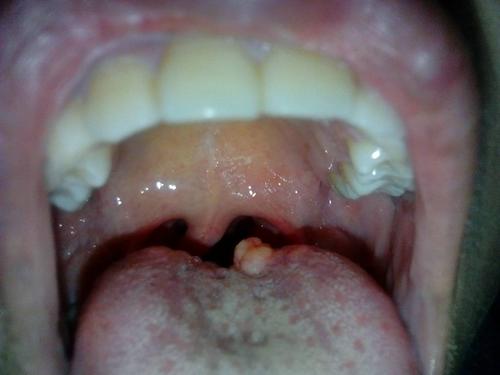

舌头下面长这个东西,很疼,这是什么?

舌头下面长了一片小肉 是什么引起的

舌头下面长了很多小肉粒是什么

舌头下长肉芽图片说明

舌头底下长肉芽图片

舌癌初期肉芽图片

舌头根部长了凸起肉粒